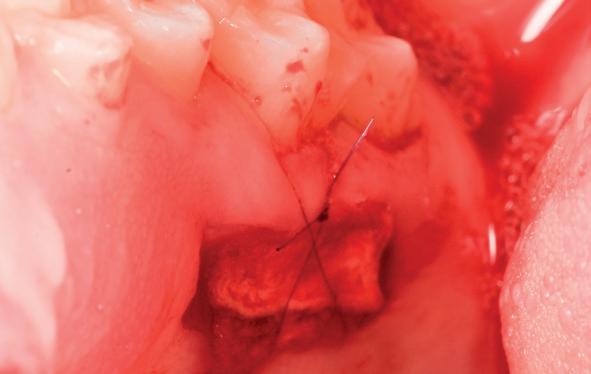

Voor de aanvulling zachte weefsels chirurgie werd gekozen voor de VISTA techniek, hierbij worden er twee incisies partial thickness flap hoog in de mucosa gemaakt, waarna er ruimte vanuit de incisies wordt getunneld tussen de gingiva en het periost door middel van VISTA tunnel instrumenten. Uit het palatum links werd een vrij gingivatransplantaat geoogst van 15x10 mm met een dikte van 3 mm, die voor inhechten werd geëpithelialiseerd. Als het epitheel niet wordt verwijderd, kan deze graft door

de mucosa heen groeien, dat ten koste gaat van de esthetiek. In het donorgebied wordt een collageen spons ingehecht, waardoor de patiënt daar minder last van heeft. Het bindweefsel wordt door de hul-

pincisies met hechtingen naar het buccale en coronale deel getrokken en aldaar ingehecht. Met twee incisies werd ook de emergence profile gecreëerd (afbeelding 6-13). Voor een goede genezing van het

11. Middels hechtingen het op de juiste plek trekken van het transplantaat

12. Transplantaat ingehecht